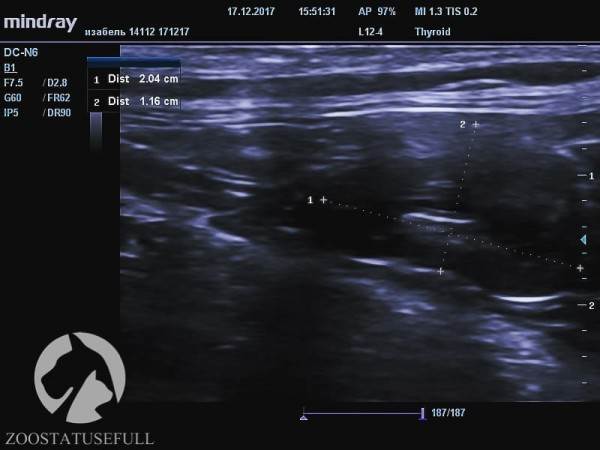

Здоровая почка кошки Изабель (обратите внимание на размер, указан в см)

Больная почка кошки Изабель

Но самое главное — воспалительный процесс, возникший в мочевыделительной системе на фоне «неотжимания» привёл к заболеванию, а потом и к «гибели» одной из почек. На снимках можно увидеть разницу между функционирующей почкой и нефункционирующей.

Это очень важно, обратите на это внимание — Изабель осталась с одной функционирующей почкой, потому что ее мочевой пузырь не опорожняли мануально, а не наоборот.